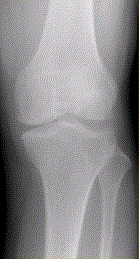

问题 患者女,54岁,右膝关节痛。实验室检查:类风湿因子阳性,除外膝关节类风湿性关节炎。X线检查结果如下图。 MRI结果如下图,诊断应为

选项 A.膝关节退行性骨关节炎 B.膝关节类风湿性关节炎 C.膝关节色素沉着绒毛结节性滑膜炎 D.膝关节滑膜型结核 E.血清阴性脊椎关节炎膝关节侵犯

答案 B